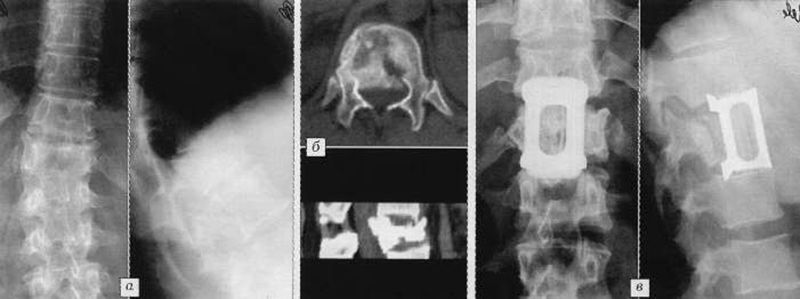

Рентгеновские снимки и медицинские изображения компрессионных переломов